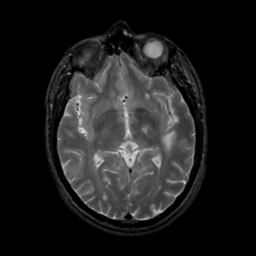

MR Study #13, May 19, 1991 -- Slice #24